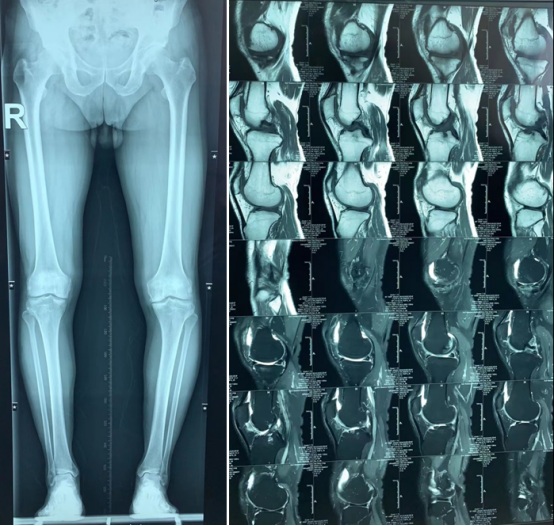

△术前及术中